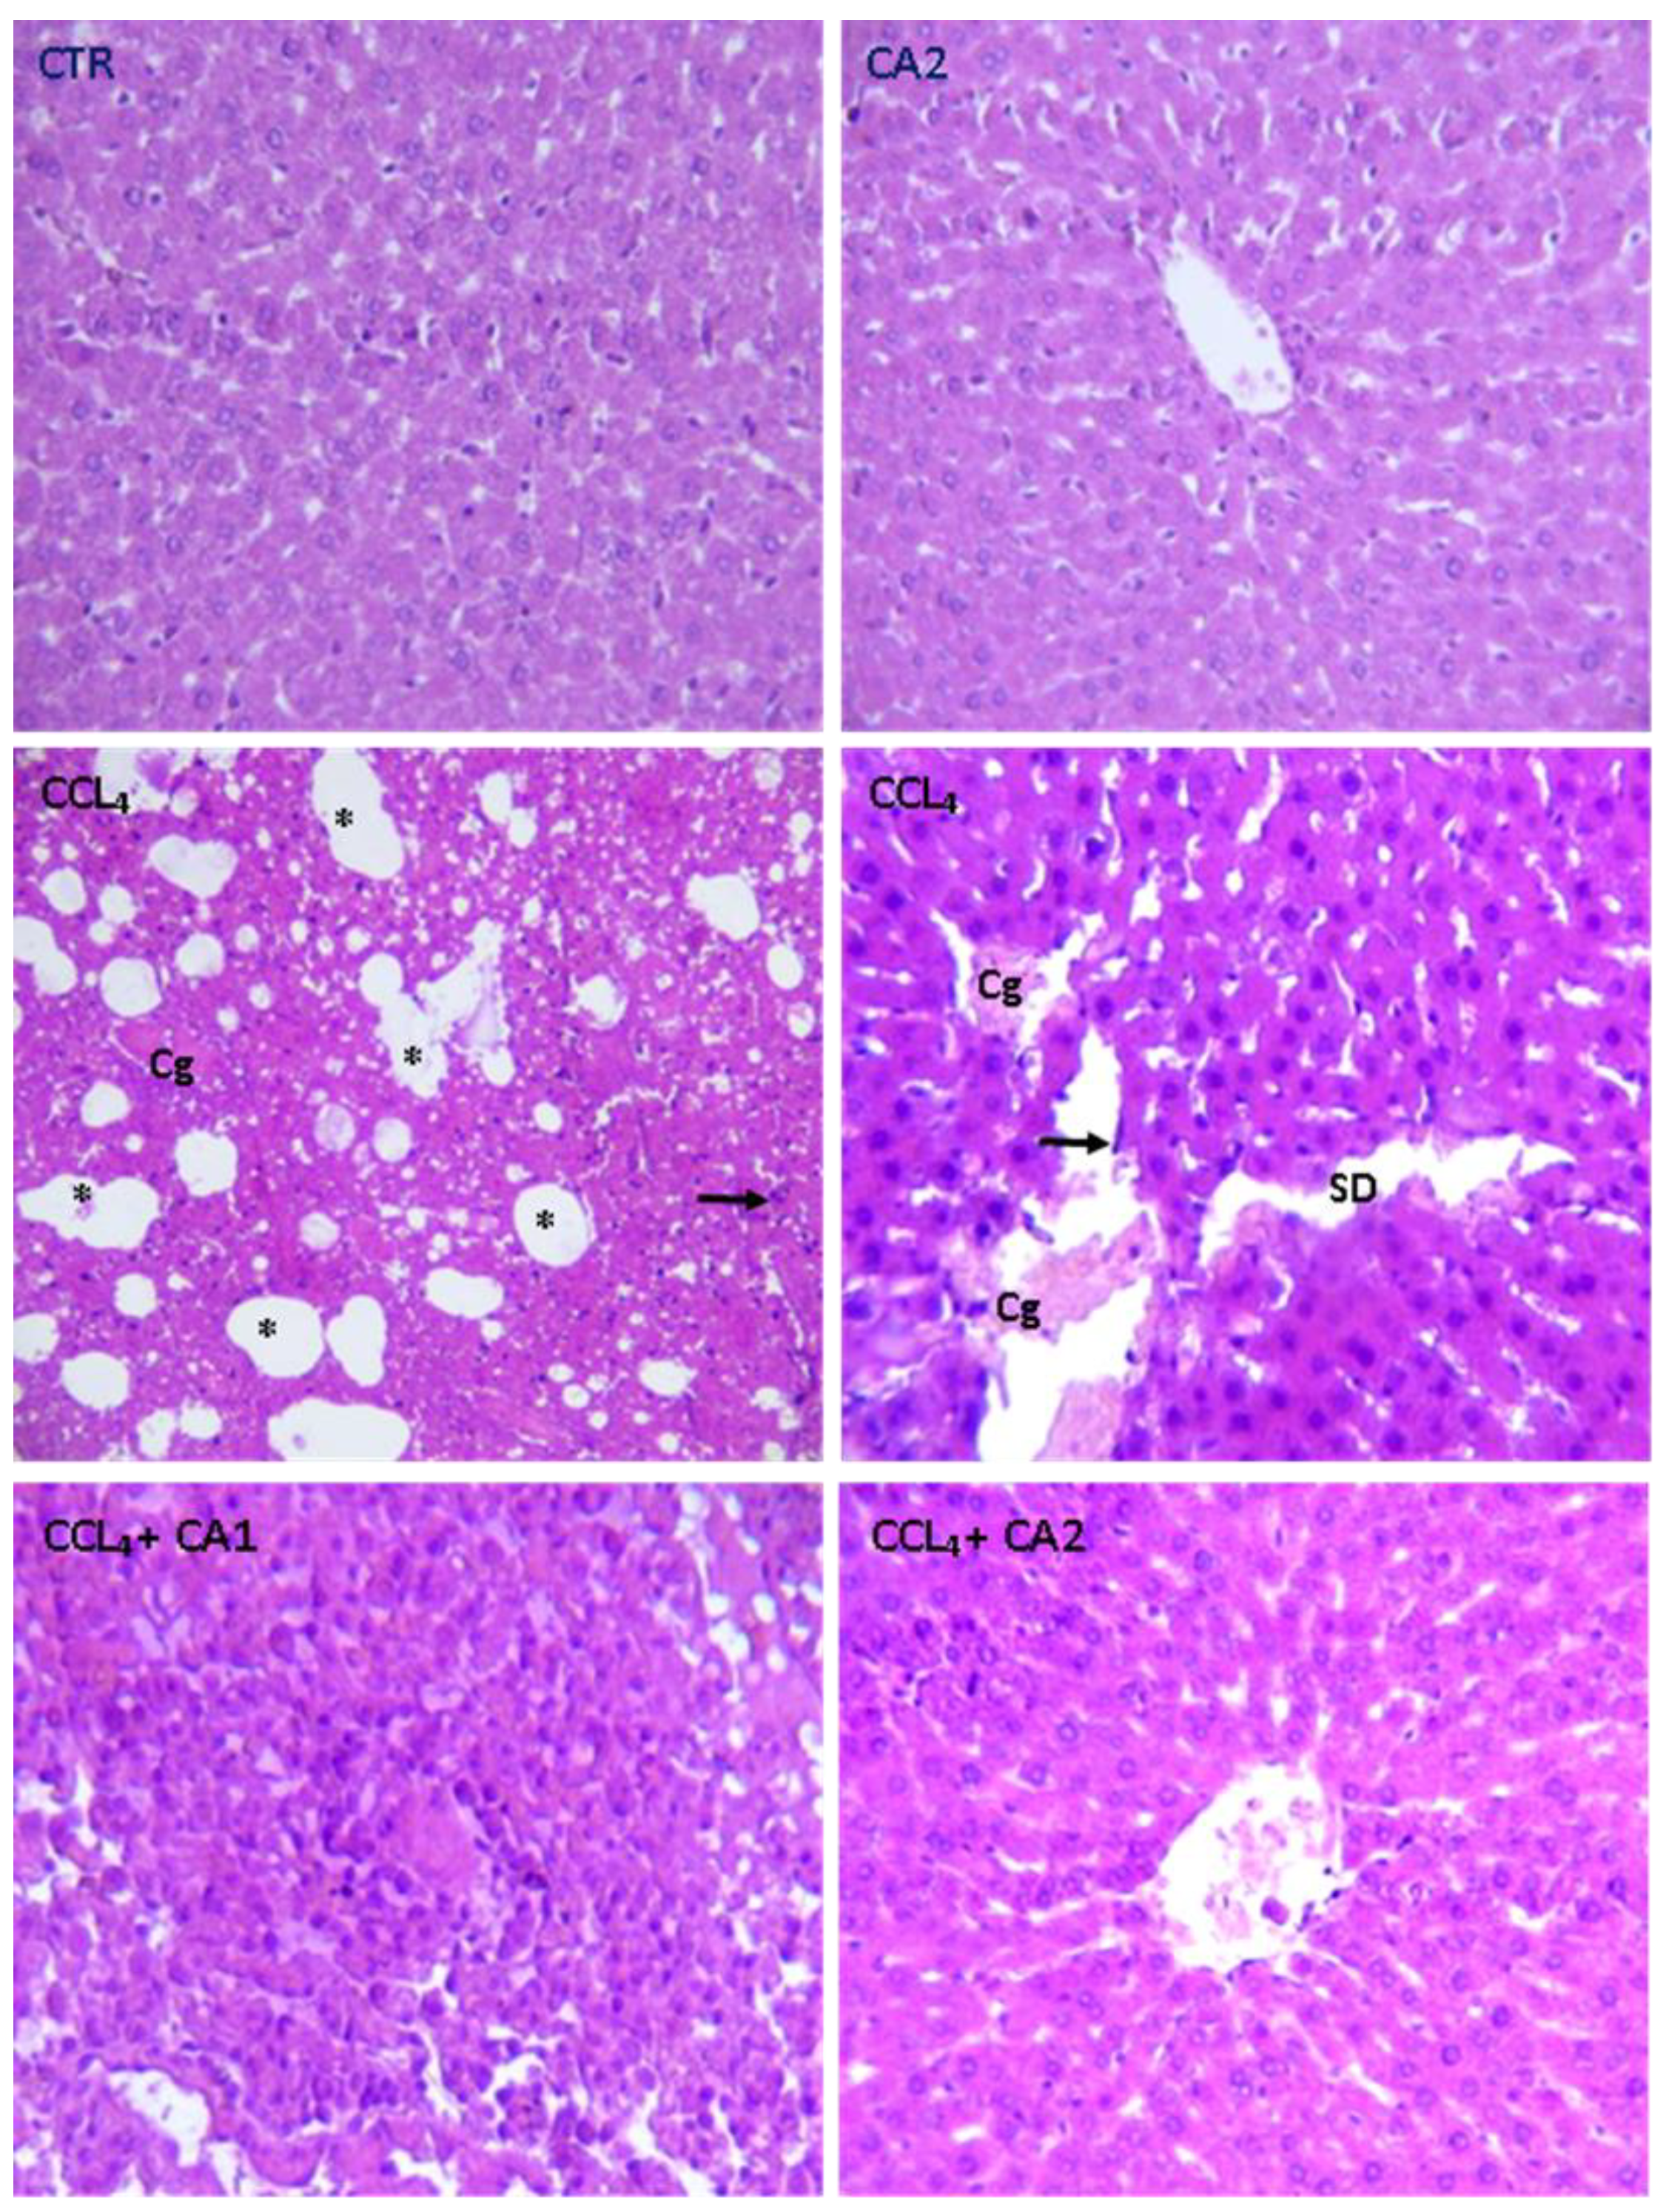

2.9. Histological Study

| Normal hepatocytes | + | + | - | - | + |

| Intact sinusoids | + | + | - | - | + |

| Sinusoidal dilation | - | - | ++ | + | - |

| Congestion of the centrilobular vein | - | - | ++ | + | - |

| Infiltration Leucocyte | - | - | ++ | - | - |

| Foci of lipid | - | - | ++ | + | - |